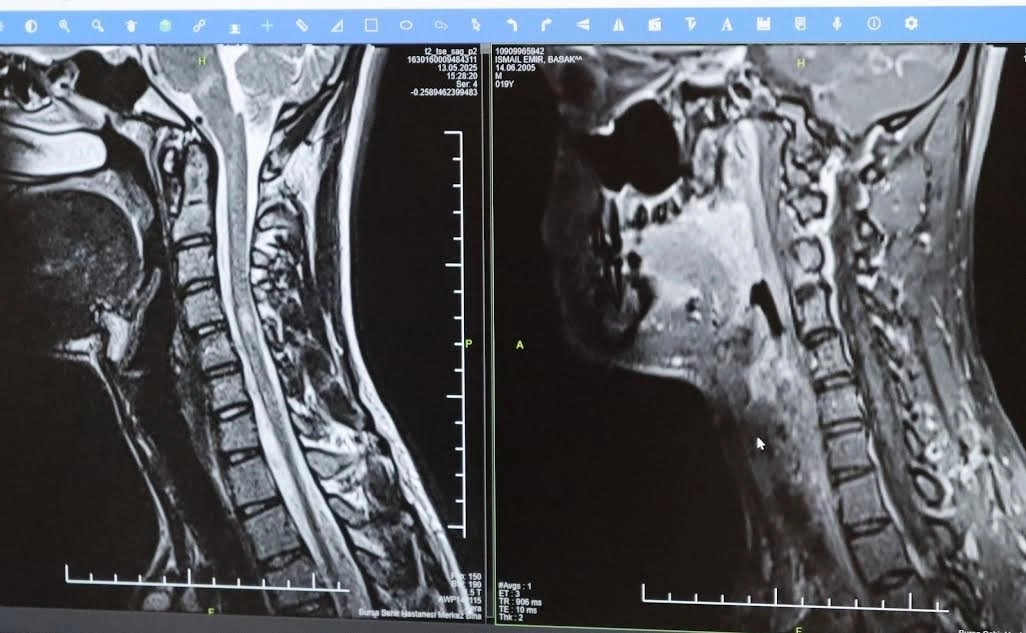

Bursa Şehir Hastanesinde görevli Nöroloji Uzmanı Prof. Dr. Özden Kamışlı, 30 Mayıs Dünya MS Günü kapsamında açıklamalarda bulundu. MS’in, bağışıklık sisteminin sinir sistemine saldırmasıyla gelişen kronik bir hastalık olduğunun bilgisini veren Prof. Dr. Kamışlı, "Dünyada yaklaşık 2.8 milyon MS hastası olduğu bilinmektedir. MS genellikle 20-40 yaş arası gençleri etkilemektedir. Bununla birlikte çocukluk döneminde ya da ileri yaşta da ortaya çıkabilmektedir. Kadınlarda görünme sıklığı erkeklere göre bir buçuk kat daha fazladır" dedi.

MS hastalarının çeşitli şikâyetlerle hekimlere başvurduğunu vurgulayan Kamışlı, "Bunlar arasında görme bozukluğu, kol ve bacakta kuvvetsizlik, uyuşmalar, dengesizlik, yürüme bozukluğu, idrar problemleri veya aşırı yorgunluk ve halsizlik hali bulunmaktadır. MS ataklarla seyredebilir ve genellikle en sık görülen formu budur. Birdenbire bir şikâyet ortaya çıkar ve zamanla azalır veya kaybolur. Bir de progresif dediğimiz ilerleyici formu vardır. Bu ilerleyici formda hastalık yavaş yavaş ilerlemektedir. MS her hastada farklı seyreder. Bu nedenle tek tip bir MS hastalığından bahsetmek mümkün değil" şeklinde konuştu.